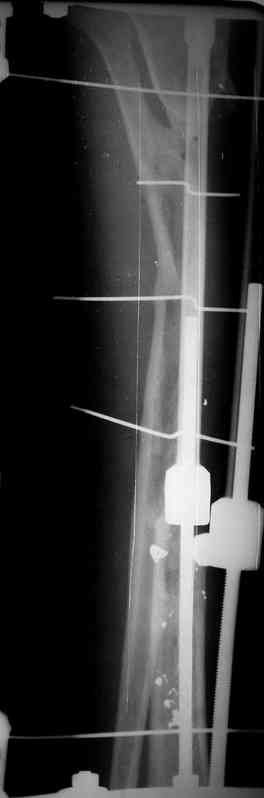

Илизарова (как придется), хирургически обработали и героически заживляли мягкие ткани с многочисленными кожными пластиками. В итоге через полгода я принял его вот таким:

Реализовал описанную выше методику, и в итоге вот что получилось. Высылаю лишь прямые проекции,

в боковых тоже всё в тему.

Очень пригодились карбоновые кольца (Джолдас -огромное спасибо, я твой должник!!!), поскольку остеопороз дистального отломка был просто невероятный. На цифровом рентгене с трудом угадывались контуры.

Рентген в процессе перемещения - внизу карбоновые кольца, тракция фрагмента спицами с упором.